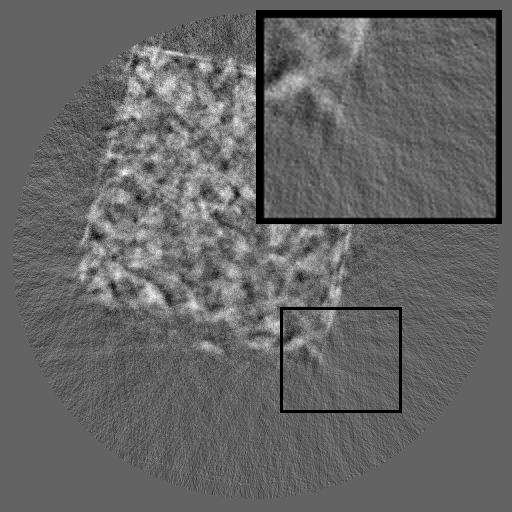

Figure 2: Qualitative inpainting results on TomoBank (lines 1 to 2) and LoDoPaB (lines 3 to 4) with random mask (ratio = 0.8) at 1024×\times1024 resolution. Odd columns and even columns show the sinograms and reconstructed images, respectively.

Inpainting Quality. Tab 2 summarizes accuracy results. At 2048×\times2048 resolution, HiSin achieves the best performance among all baselines while remaining memory-efficient, demonstrating its ability to extend high-quality inpainting to resolutions where other diffusion models fail. At 1024×\times1024, HiSin delivers accuracy comparable to its computation-intensive counterpart RePaint, showing that our optimizations do not compromise fidelity at moderate scales. Compared to DiffIR and HiDiffusion, HiSin consistently achieves higher SSIM and PSNR across mask ratios, with improvements up to +0.03 SSIM and +1.8 dB PSNR. Fig 2 visualizes sinogram inpainting and reconstructed images, where HiSin produces nearly indistinguishable results from RePaint. These findings confirm that HiSin fundamentally extends diffusion-based inpainting to 2048×\times2048 resolution in a more memory- and runtime-efficient manner.